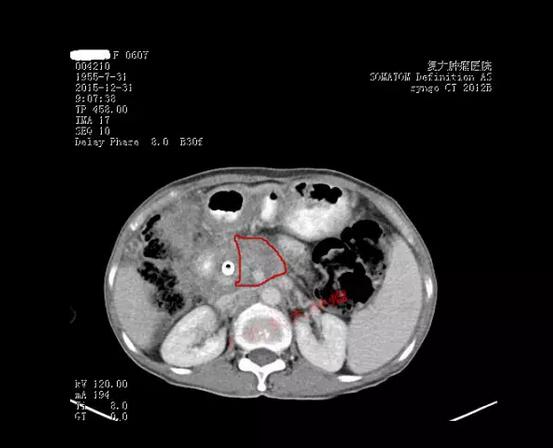

患者的CT检查结果

陈女士的手术很顺利,CT加B超双引导双监测,肿瘤消融达到了90%以上。目前患者已经顺利脱离呼吸机,病情平稳,今天已离开ICU回到普通病房。我们计划几天后开始给予其他的抗肿瘤治疗,包括微血管介入和肿瘤免疫治疗。希望通过我们的努力,能给这位晚期胰腺癌患者更多的生存机会。祝福她!